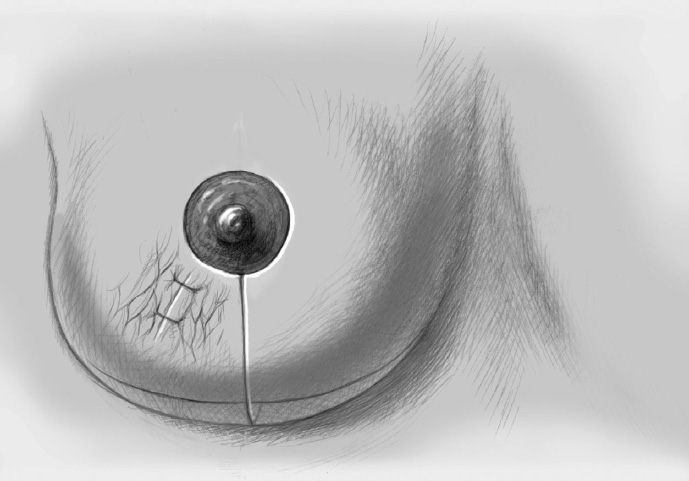

The skin is closed in two layers with recentering of the nipple–areola complex using interrupted sutures (Vicryl 3–0) according to the preoperative de-epithelialization pattern, which can be corrected at this time.

The skin is closed with an intracutaneous continuous monofilament suture.

Local radiotherapy is mandatory after breast-conserving tumor resection; this is what constitutes breast-conserving therapy. The need for systemic postoperative treatment is guided by the final TNM status and depends on tumor size, nodal status, and histological parameters. The patient should mobilize promptly postoperatively with early drain removal (when secretion is < 30–40 mL/24 h) and also appropriate physiotherapy following more extensive procedures. Every patient should be seen again 10 to 14 days postoperatively and before the start of further treatment (radiotherapy and/or chemotherapy). If there has been a substantial reduction in ipsilateral breast volume, the healthy breast can be altered either during the primary surgery or following conclusion of the radiotherapy and/or chemotherapy, according to the patient’s wishes.